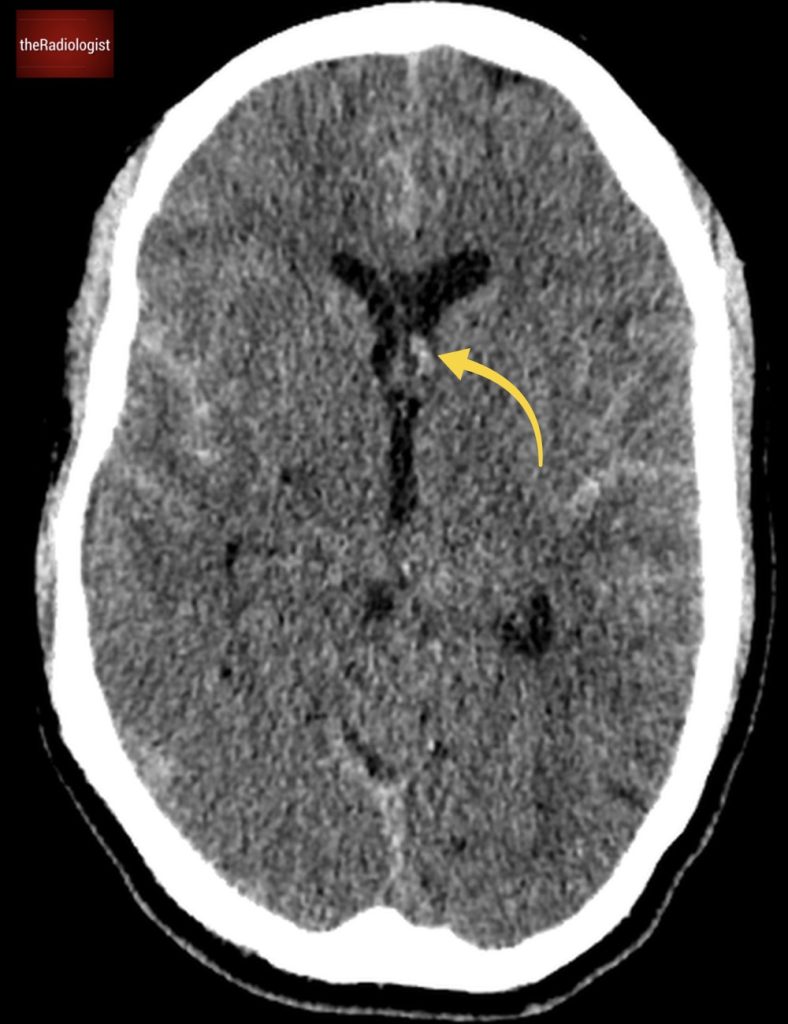

Case 9

A male in his 50s presents to the ED with back and abdominal pain as well as a fever. He has a post contrast CT of his abdomen and pelvis in a portovenous phase. What is the most likely diagnosis?